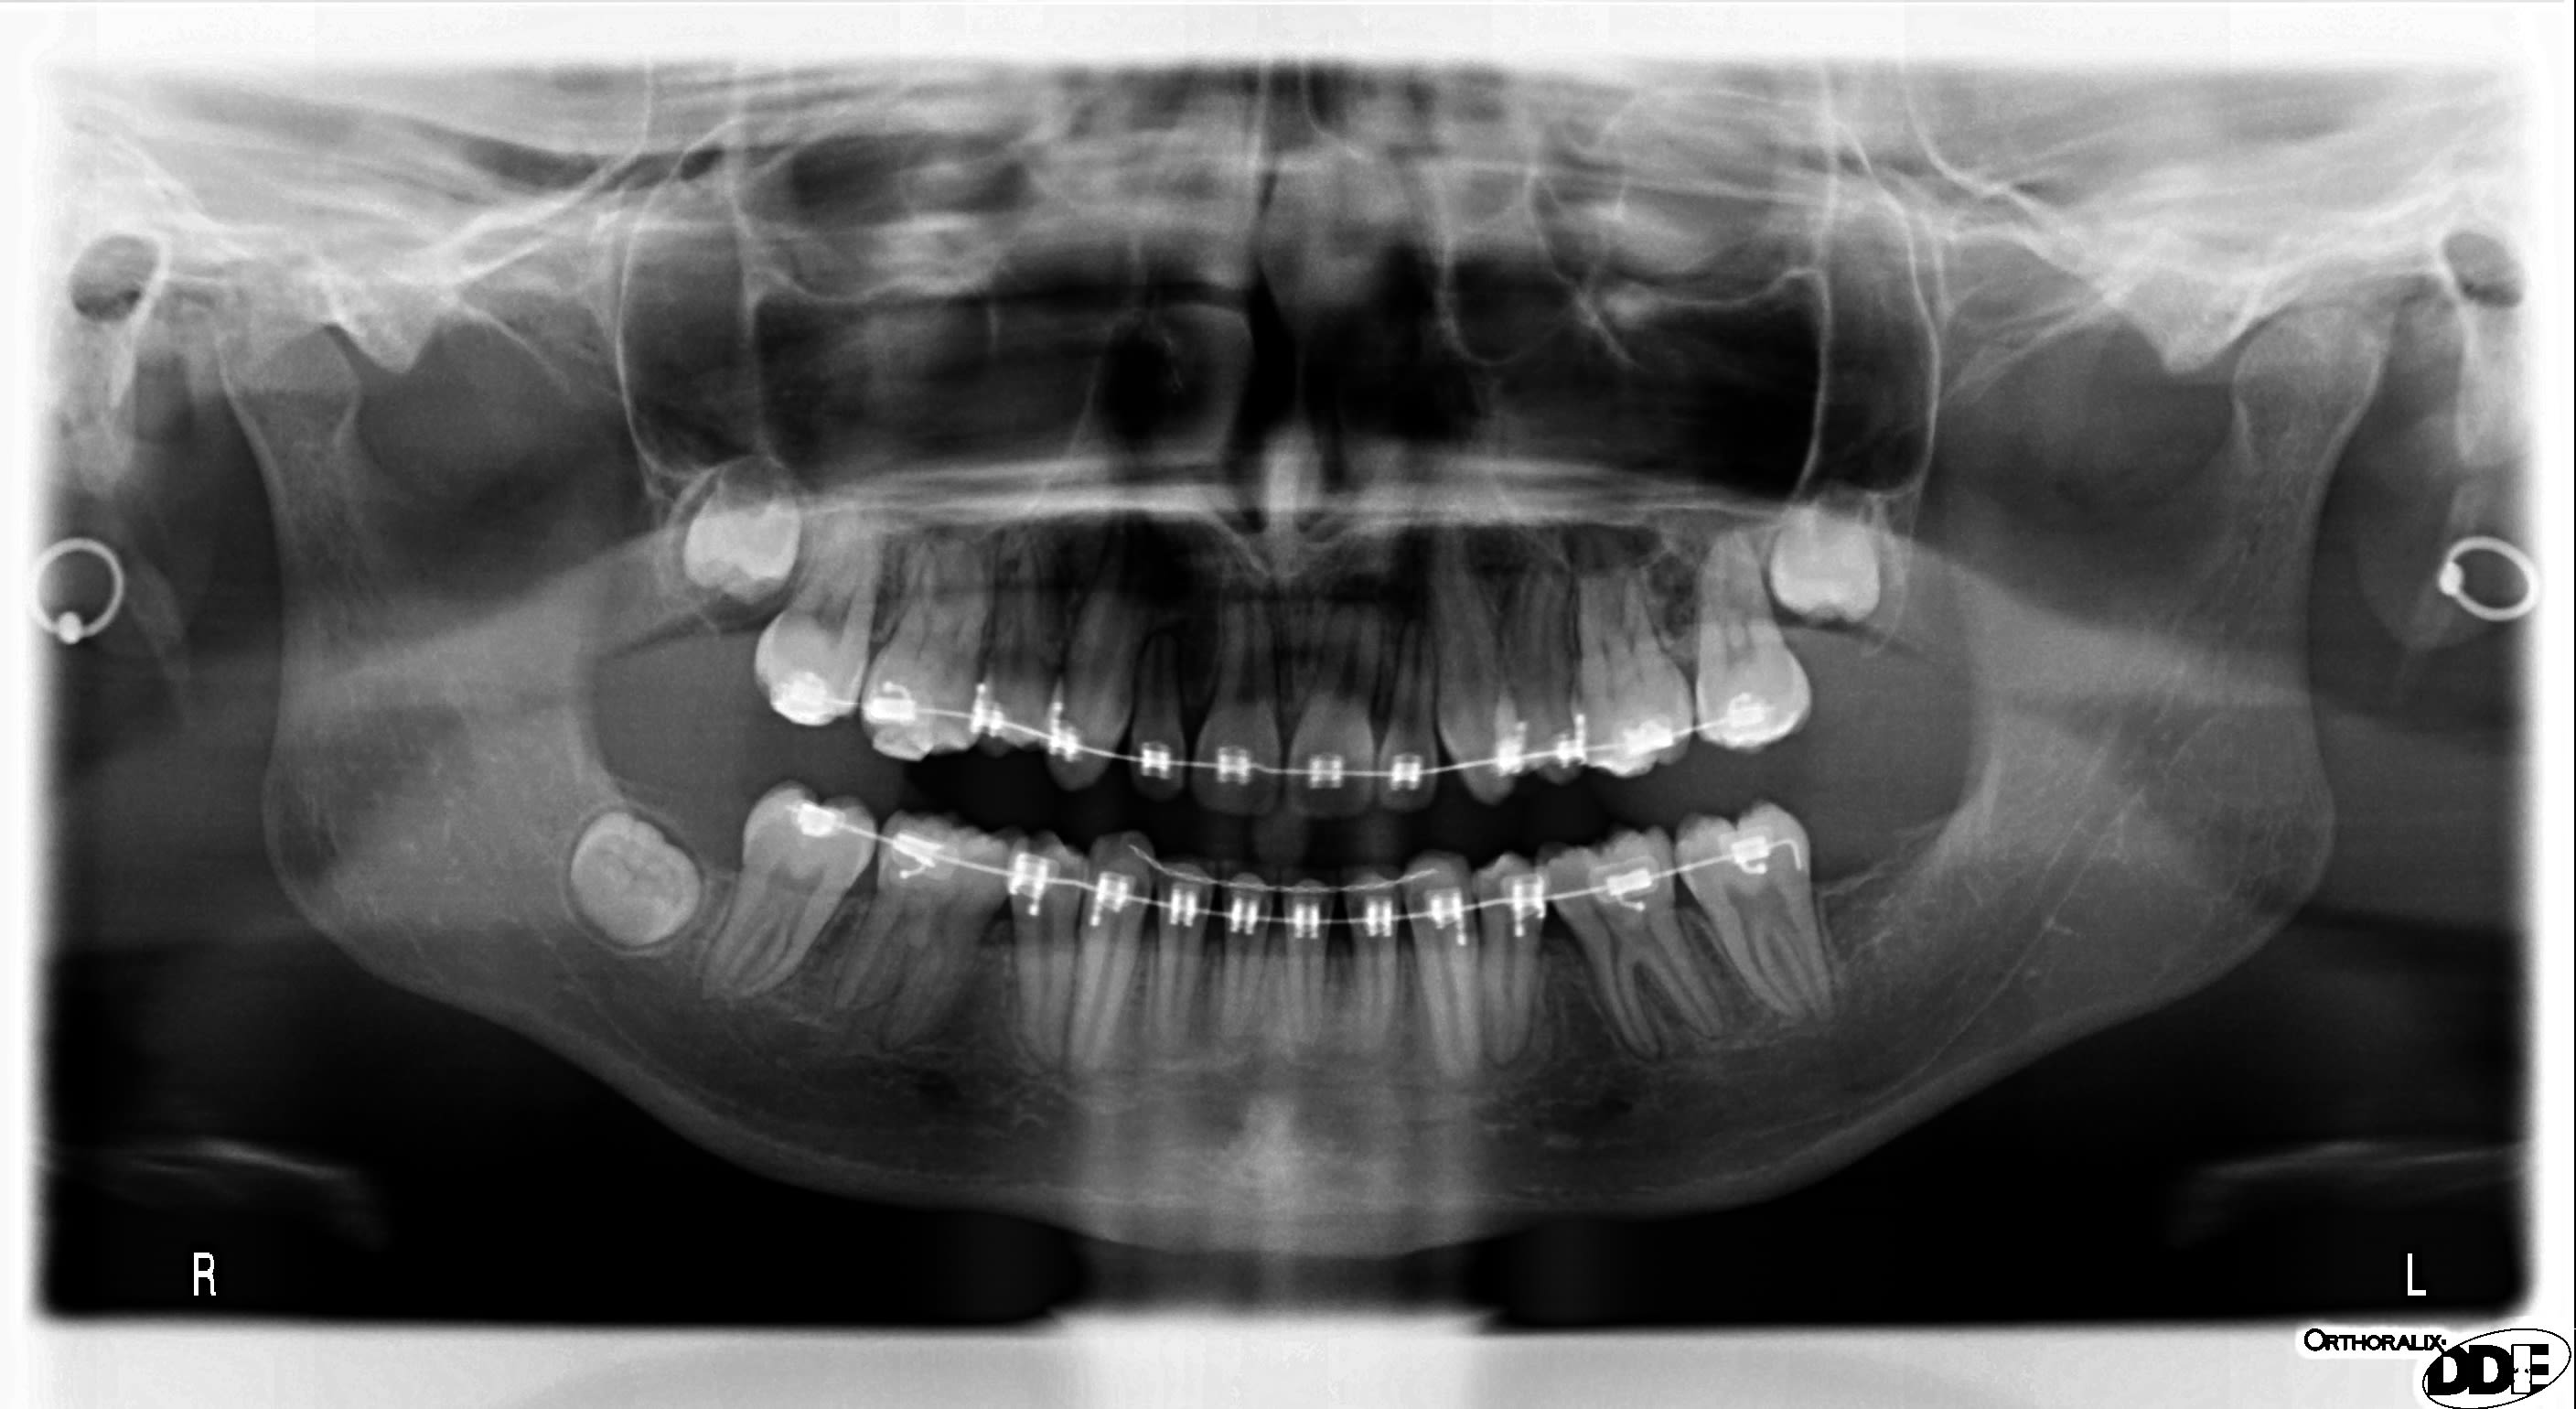

Une de mes jeunes patientes (17 ans), en fin de traitement orthodontique, présente encore 2 diastèmes persistant entre 12-13 et 22-23.

Elle avait une classe 2 squelettique associée à une dysmorphose dentodentaire ainsi qu’une dysharmonie dentodentaire et une proalvéolie des incisives supérieures et inférieures. Je vous joins les 3 panos faites en 2015/2018 et 2020.

La consoeur qui a repris le traitement depuis fin 2019 a refait une pano en mai à la patiente et au vu des racines des incisives max envisage de débaguer cet été en laissant les espaces non refermés et en suggérant de recourir à des facettes pour corriger au niveau esthétique.

Mais j'ajouterai quand-même que JUSTE au regard de la pano de mai, le traitement en soit est déjà loin d'être terminé (orientation des racines,...) !

Je reviens sur le commentaire d'emily, oui le ttt est très loin d'être terminé (orientation des racines canines, pms…), quid DDS ?, et résorption radiculaires I Sup ???